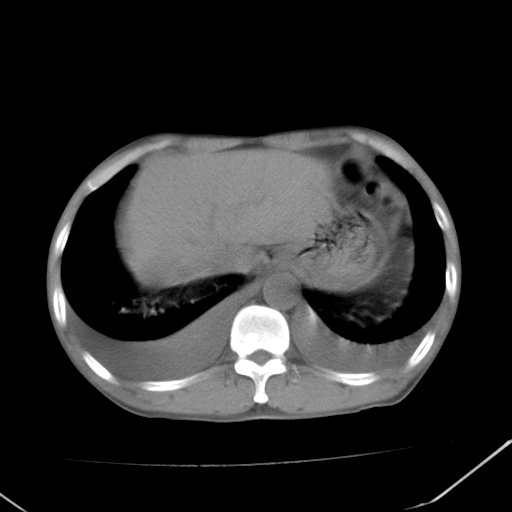

谢谢各位指导。刚才急查肾功能结果:肌酐1000多。尿毒症。

双肺野对称性磨玻璃影,分布于内中带,双侧胸水,患者有咯血。

双肺野广泛对称性磨玻璃影、实变影,以肺门为中心,主要分布于内中带,符合典型肺泡性肺水肿;伴双侧胸腔少量游离积液。结合患者既往病史且咯血就诊,支持多因素(尿毒症等)所致之肺水肿、肺出血、胸水;影像表现暂不考虑心源性水肿,且症状也不太符。需密切随诊结合临床治疗等进一步明确。